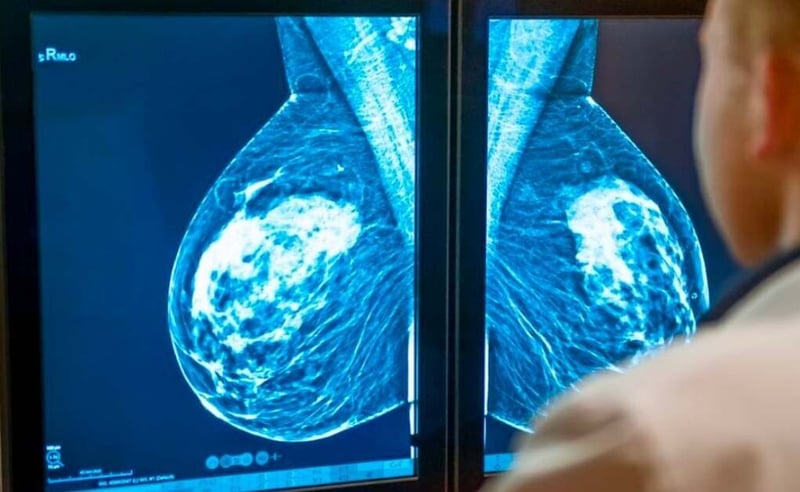

Breast cancer is a significant health concern for women worldwide, emphasising the importance of early detection through screening. Mammograms, X-ray examinations of the breast, play a vital role in detecting breast cancer in its early stages. However, determining the appropriate age to start having mammograms is a topic of ongoing discussion and depends on various factors. In this blog, we will explore the current guidelines and considerations for when to begin mammogram screenings.

Understanding the Guidelines:

Different organisations and medical societies provide guidelines for mammogram screening, but there is some variation in their recommendations. Let’s explore the general guidelines: